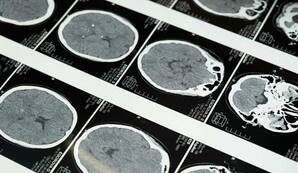

Гематолог Висо объяснил сложности с походкой после алкоголя процессами в мозге

Согласно объяснениям доктора, мозжечок является центральным элементом в поддержании баланса.Царьград

Кроме того, доктор отметил, что размытое зрение после алкоголя также связано с нарушениями в работе мозга.Радио 1